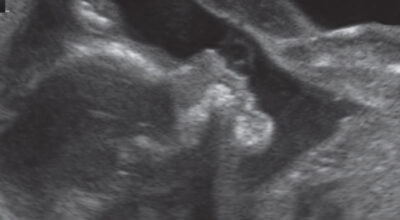

La evolución del feto a través de ecografías

Ecografía de 4 meses: dos manos cruzadas.